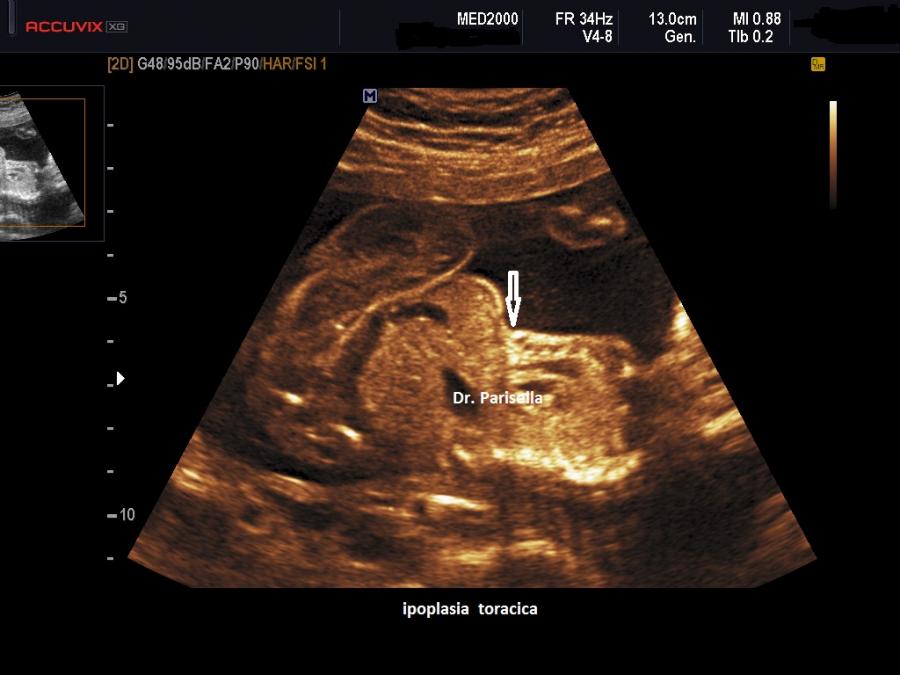

All'esame ecografico prenatale le caratteristiche che indirizzano verso la diagnosi sono:

2) l'ipoplasia toracica è di media entità ed è legata alle coste corte